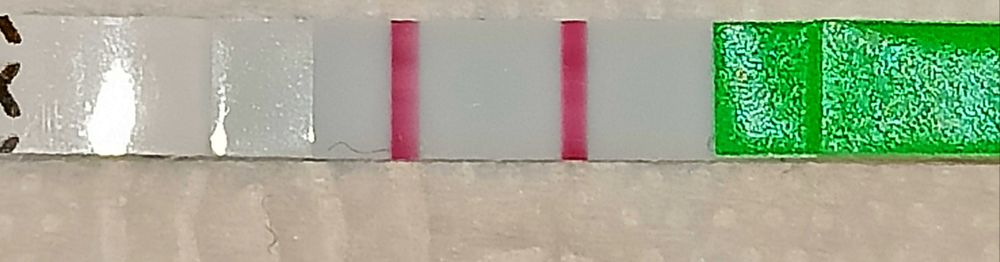

Не ярчают ...

Тесты на О. 17-18д. ц. Когда же будет овуляция? И будет ли...

В пик тестовая ярче контрольной на 200% должна быть :

Или хотя бы на 100%:

Или хотя бы на 100%:

Или хотя бы на 100%:

Или хотя бы на 100%:

Вахш

Потешка, тесты у вас ярчают. Последняя полоска снизу уже похожа на овуляцию. Следующий тест может уже не показать полоску вообще. Такой же яркой, как контрольная полоска, тестовая полоска не будет.

Ирина, нет, эти тесты на много ярче выдать должны

Сегодня полоска будет яркая,но не положительная ,а завтра вообще не быть,а через пару дней резкий скачок ЛГ и вуаля,автор,продолжайте отслеживать ,это еще не пик

Не переживайте, это не как тест на беременность, который ярчает постепенно. Они прям резко должны выдать яркую полоску 😉